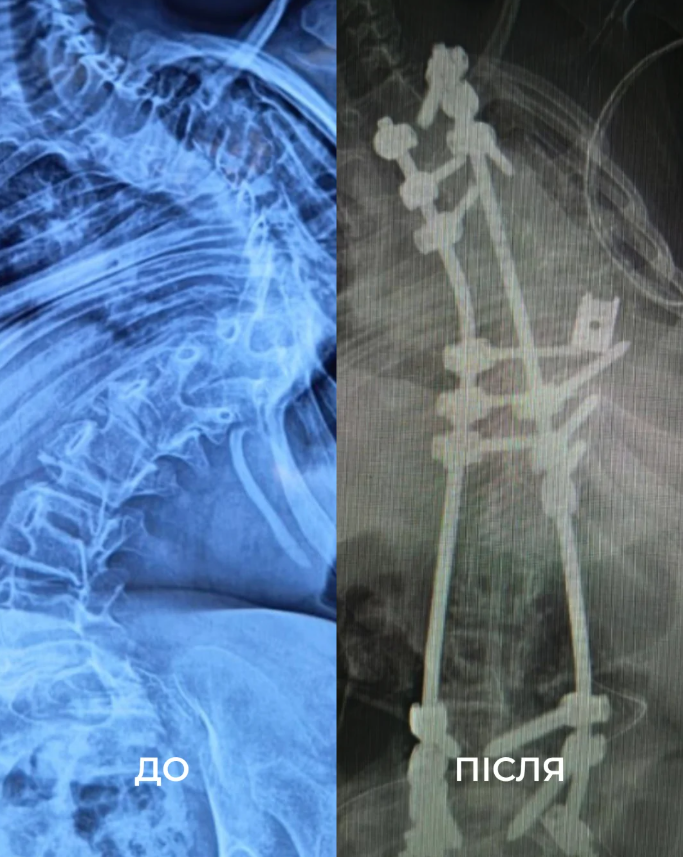

12-річна дівчинка зі Східниці (Львівщина) перенесла дві складні операції поспіль, які тривали 18 годин під наркозом. Завдяки втручанню львівських та американських лікарів їй вдалося випрямити хребет на 85%.

У дитини діагностували сколіоз IV ступеня, спричинений рідкісним захворюванням міопатією Бетлема. З роками її стан погіршувався – хребет дитини викривився аж на 160 градусів, вона відчувала постійний біль та пересувалася лише з ходунцями чи у кріслі колісному.

"Щоб виправити її сколіоз, нам потрібно було видалити цілий хребець. У перший день операції ми закріпили її хребет гвинтами. А потім уже на другий день видалили кілька ребер, ізолювали спинний мозок та встановили титанову клітку", розповів Диржка.

Врешті дівчинка провела 18 годин під наркозом. Хірургам вдалося вирівняти хребет дівчинки на 85%